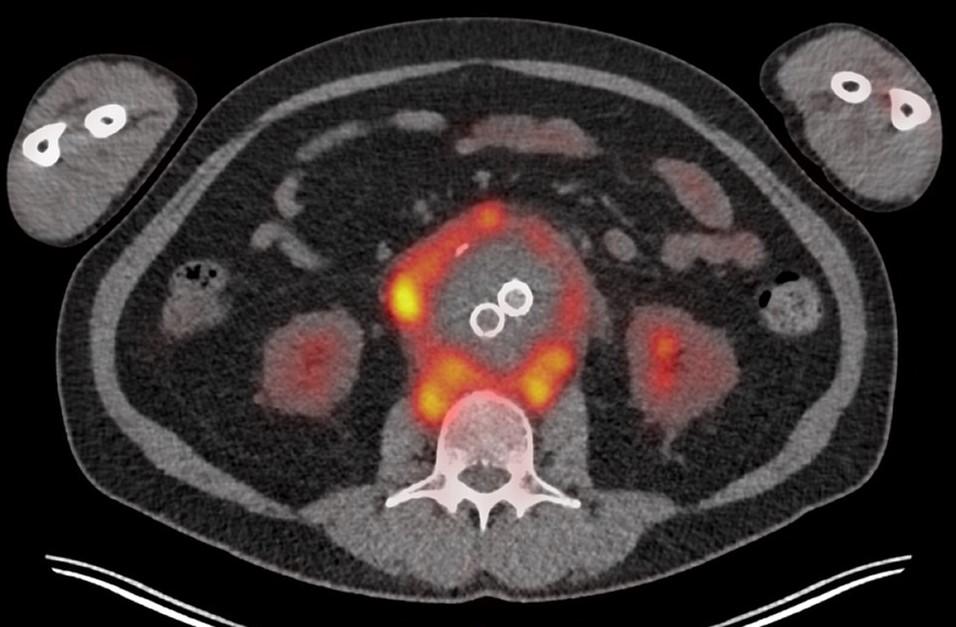

Een 65-jarige vrouw heeft enkele weken eerder een endovasculaire behandeling ondergaan vanwege een abdominaal aorta-aneurysma. Sindsdien heeft zij aanhoudend een subfebriele temperatuur. Bij laboratoriumonderzoek zijn de ontstekingsparameters licht verhoogd.